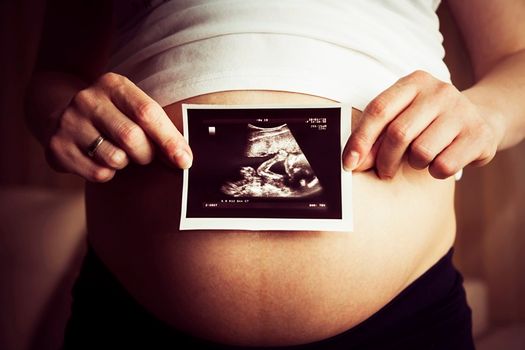

A Kansas couple have shared a heartbreaking ultrasound image of their unborn son holding the hand of his twin sister in utero.

As the devastated couple watched their son’s health worsen, a beautiful moment captured on a routine sonogram offered a small glimmer of hope. The image clearly shows Mason’s tiny hand wrapped around his sister’s finger.

“We didn’t really see much, she said there’s his hand and there’s her hand and it looks like they’re holding hands,” Brittani said.